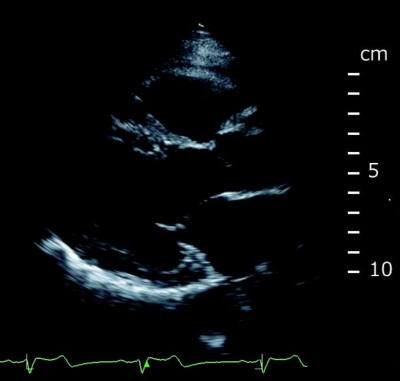

血液所見:赤血球414万、Hb 12.6g/dL、白血球5,400、血小板27万。血液生化学所見:総蛋白7.4g/dL、アルブミン4.3g/dL、AST 21U/L、ALT 22U/L、LD 261U/L(基準120〜245)、CK 78U/L(基準30〜140)、クレアチニン0.5mg/dL。CRP 0.1mg/dL。胸部エックス線写真で異常を認めない。心電図で完全房室ブロックを認める。心エコー図を別に示す。左室駆出率は45%であった。完全房室ブロックに対して一時的ペースメーカーを挿入した。